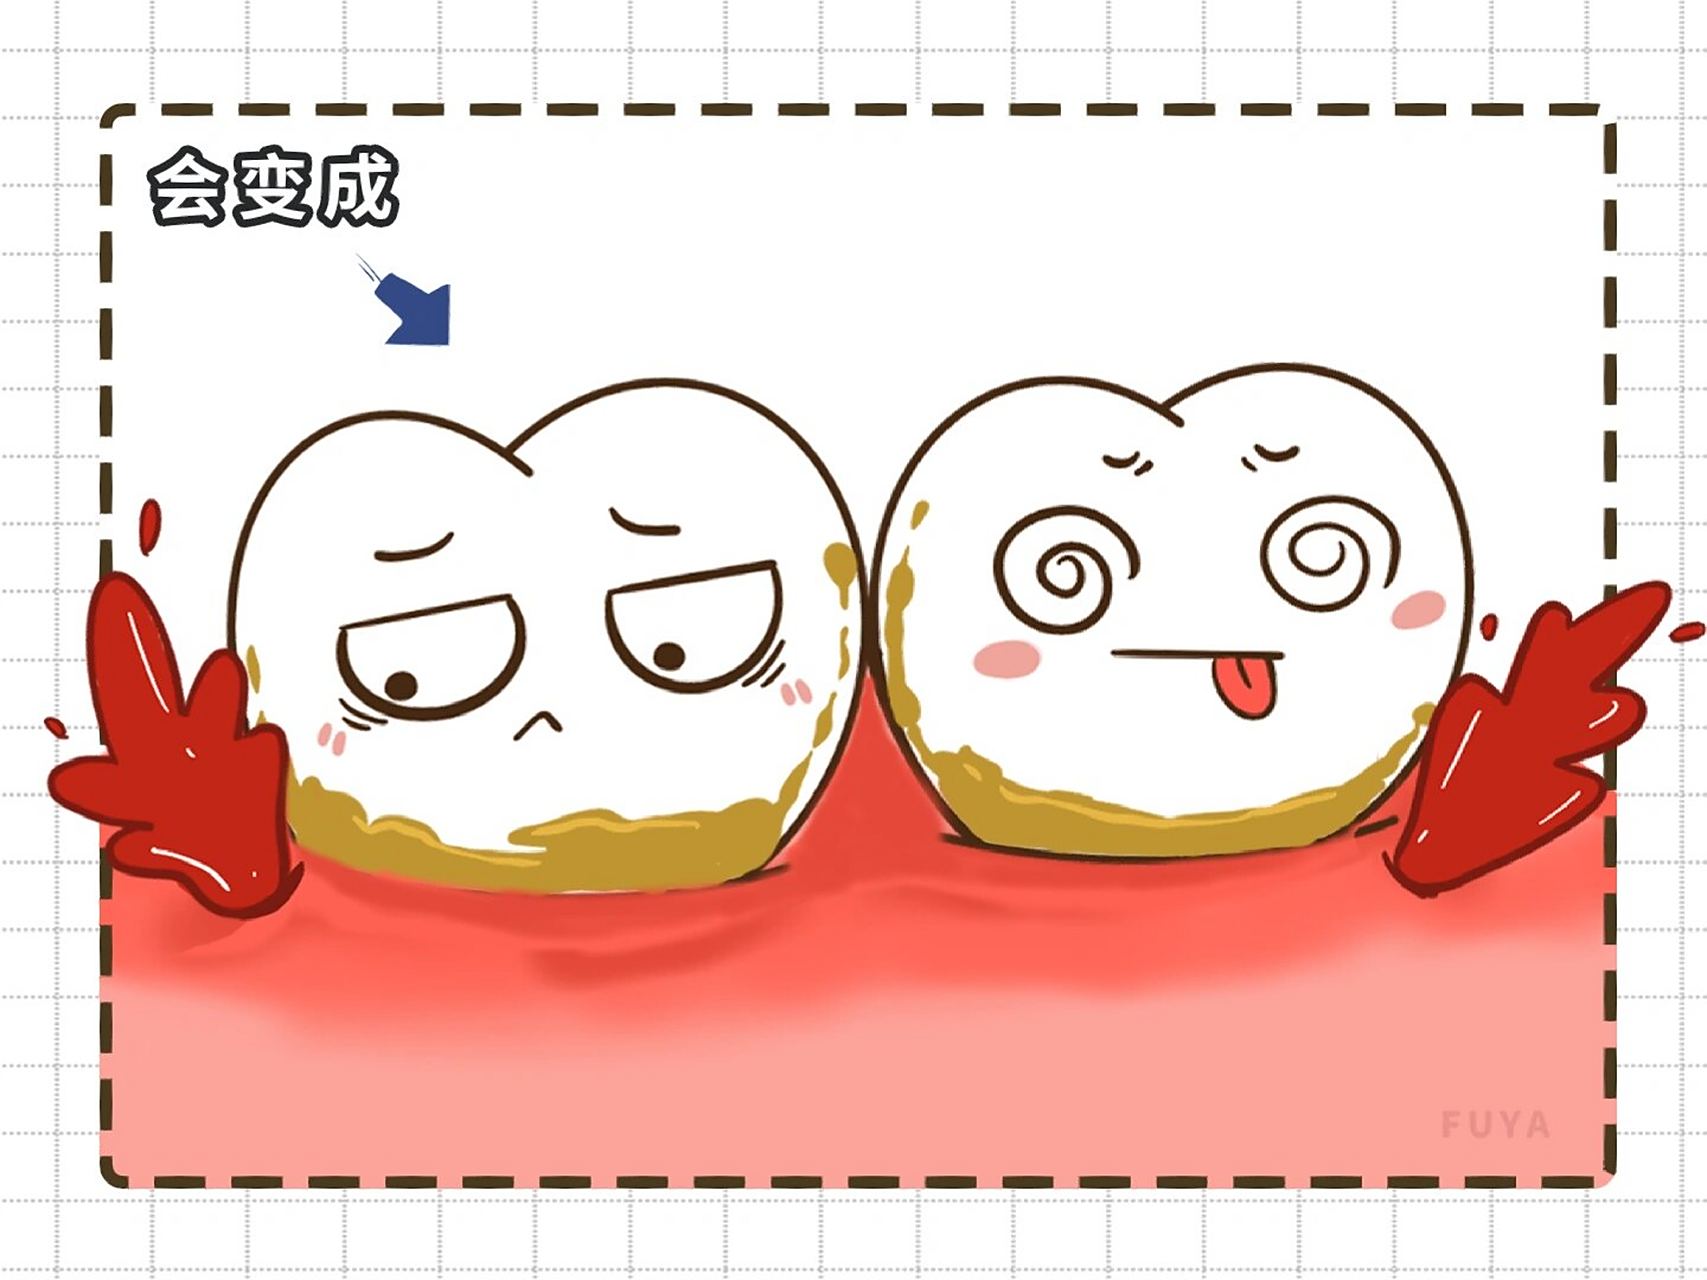

牙龈结石竟然这么可怕?

图片尺寸845x1053

牙结石如何一步步"攻占"牙齿 牙结石由牙菌斑钙化沉积形成,是口腔健康